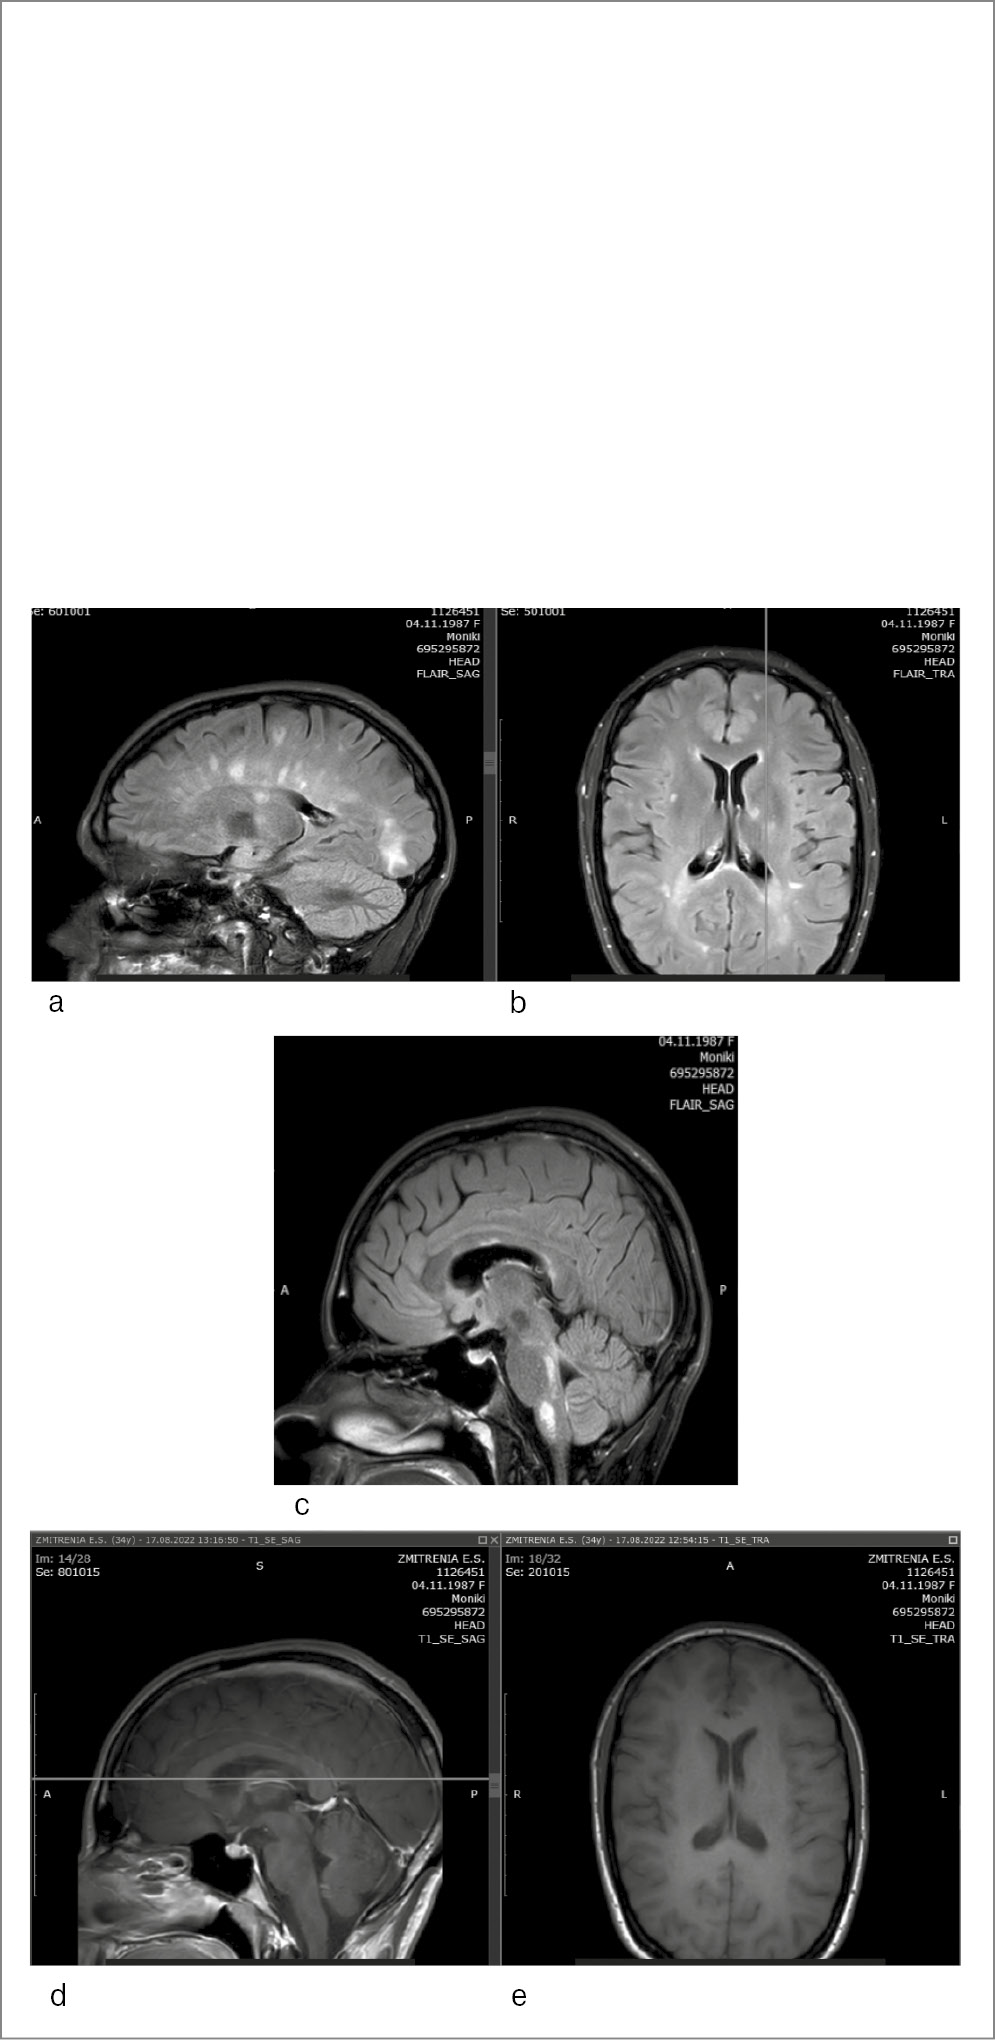

Пациентка З., 36 лет, диагноз РС, ремиттирующее течение, установлен 6 лет назад, рекомендован интерферон β-1а. На фоне проводимой терапии сохранялась активность заболевания. Пациентка переведена на ежемесячное введение НТЗ, индекс титра АТ к JCV в сыворотке крови 0,51. Состояние стабилизировалось, нежелательных явлений не регистрировалось. Проведено 18 введений и лечение НТЗ остановлено на 30-й неделе беременности (следуя рекомендациям на тот момент по ведению беременных на терапии НТЗ). Роды срочные, самостоятельные, здоровый мальчик: 3490 г, 53 см, по шкале Апгар 8/9. Выполнено МРТ головного мозга через 10 дней после родоразрешения, выявлены контрастируемые очаги на Т1-взвешенных изображениях, клинически пациентка оставалась стабильной, проведена пульс-терапия метилпреднизолоном 3000 мг на курс. Возобновлено введение НТЗ, при повторном исследовании сыворотки крови индекс титра АТ к JCV 0,44. В дальнейшем состояние оставалось стабильным, контроль крови на индекс титра АТ к JCV проводился 1 раз в 6 мес, МРТ головного мозга 1 раз в 12 мес (рис. 2). После родов пациентка получила 25 введений НТЗ (всего проведено 43 инфузии), когда при плановом исследовании анализа сыворотки крови на индекс титра АТ к JCV отмечено его повышение до 1,31. Пациентка жалоб не предъявляла, в неврологическом статусе без изменений. Выполнено МРТ головного мозга (рис. 3), заподозрена ПМЛ, лечение НТЗ остановлено.

Рис. 2. МРТ головного мозга пациентки З. за 12 мес до НТЗ-ПМЛ. Исследование проведено на высокопольном аппарате с индукцией магнитного поля 3 Тесла. Изображения получены в аксиальной и сагиттальной плоскостях до и после контрастного усиления: а, b – в режимах T2ВИ, FLAIR; c, d – в режиме T1ВИ. МРТ-картина многоочагового поражения вещества головного мозга с супратенториальной и инфратенториальной локализацией очагов, с вовлечением в процесс мозолистого тела, без признаков нарушения ГЭБ.